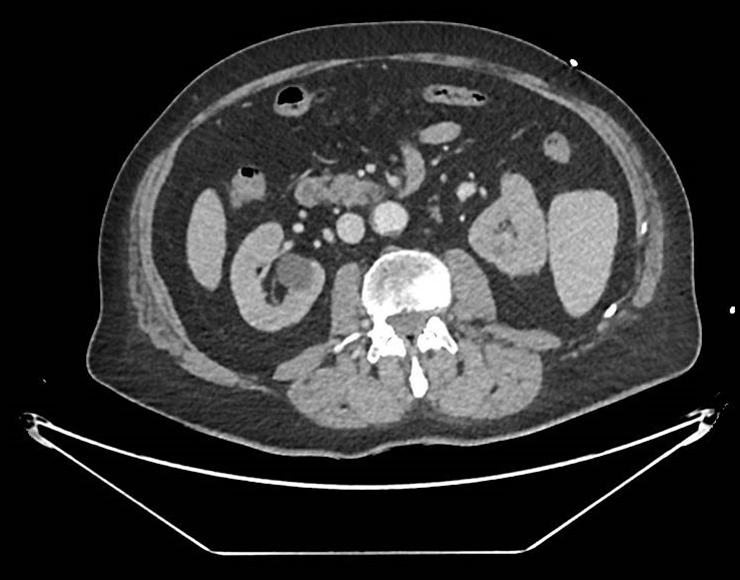

À l’examen clinique, il a des marbrures diffuses, une pâleur, des extrémités froides, un ictère cutanéo-muqueux diffus, une auscultation pulmonaire parfaitement claire, un abdomen souple et indolore. Le reste de l’examen est sans particularité. Le patient signale des urines anormalement foncées.